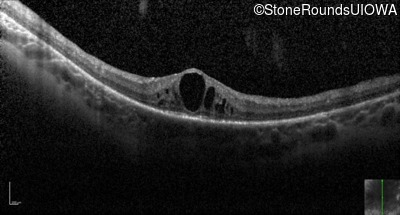

Optical Coherence Tomography - Left - 20/70 +1

Exemplar / OCT Stack